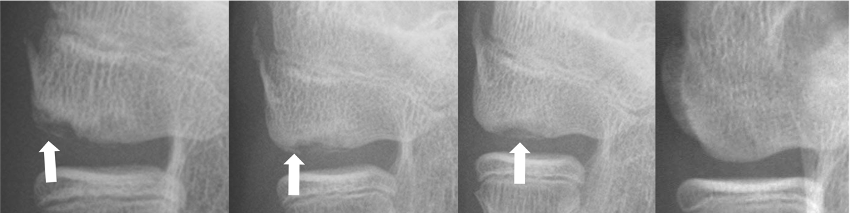

単純X線

骨が透けたり骨のラインが連続していない状態が確認できます。X線で病気の段階を3つに分類します。(透亮期・分離期・遊離期)

X線分類

超音波診断(エコー)

初期に発見するために有用な検査です。単純X線でわからないようなものまで診断可能です。侵襲がなく持ち運び可能であるためスポーツ検診で使用されます。

正常では骨のラインが綺麗に見えるが、OCDになると乱れているのがわかる